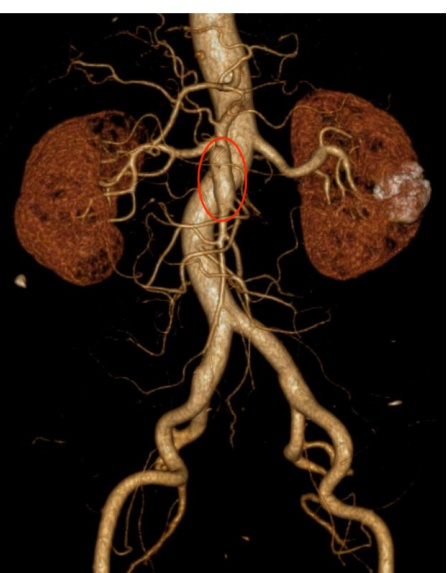

17:03,腹部血管CTA完成。很快,初步结果出来了——考虑肠系膜上动脉夹层动脉瘤形成。那一刻,这场困扰了钱先生整整两年的“胃痛”,终于被揭开了真相。

很多人对这类疾病并不熟悉,但对医生来说,这已经是一个必须争分夺秒处理的信号。因为肠系膜上动脉一旦发生夹层并形成动脉瘤,潜在风险很高,如果不及时治疗,动脉瘤可能会破裂,引发剧烈腹痛、大量出血,甚至危及生命。

19:30,龚淞楠医生陪同患者及家属抵达嘉定院区急诊,并顺利完成交接。患者当时整体病情稳定,当晚入住血管外科,接受进一步评估和治疗。在排除相关禁忌后,11月4日,血管外科孙羽东副主任医师为患者实施了肠系膜上动脉夹层腔内隔绝+假腔栓塞术。